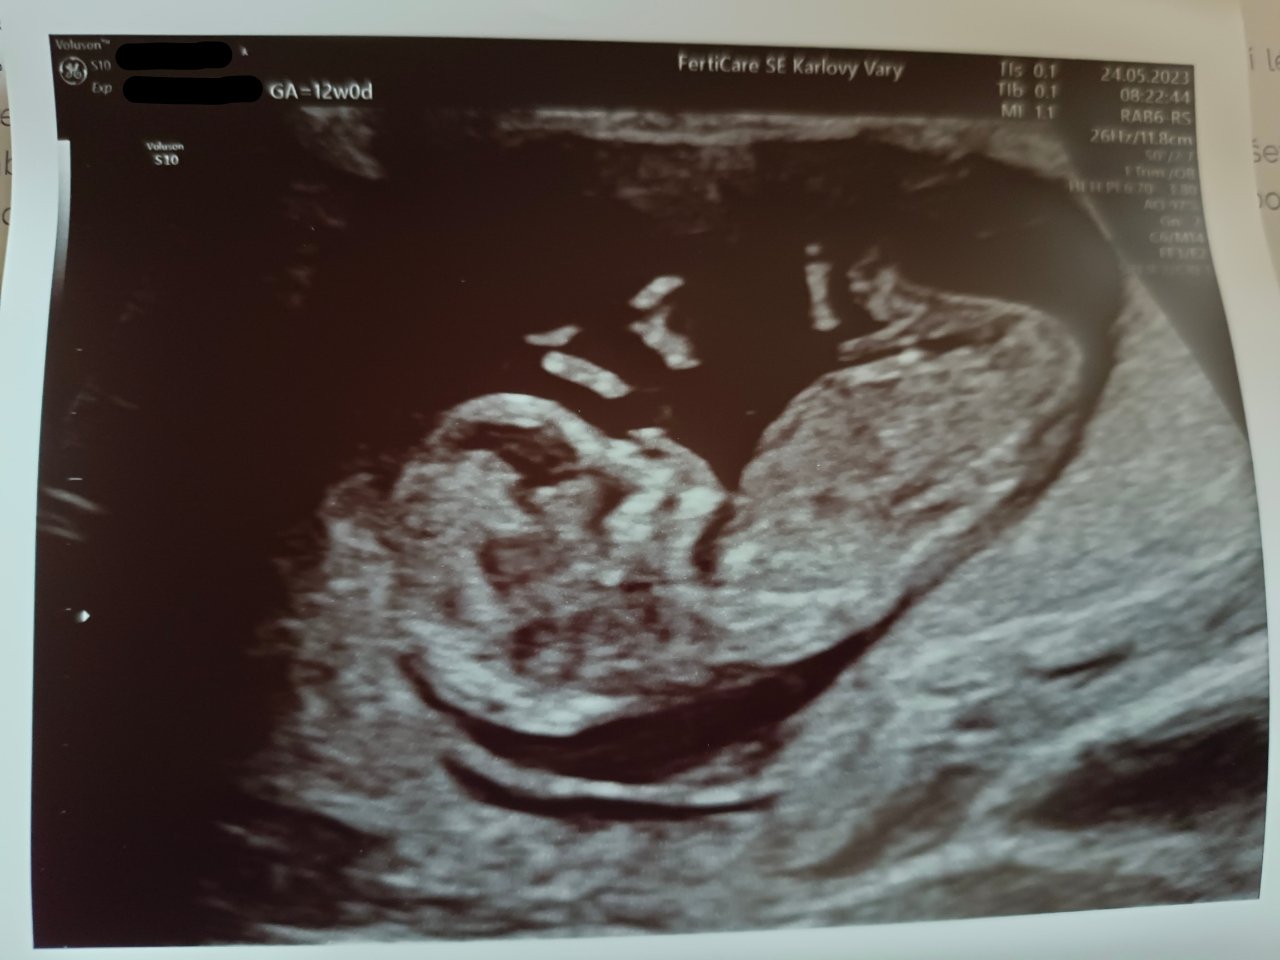

@zuzanaa2010 ahoj, ja som sa tu sem tam dostala a odpovedala na nejaké otázky dievčat, ale o sebe som nepísala 🙂 som 12+2 a zatiaľ to vyzerá ok, v stredu som mala 1trimestrálny screening a čakám ešte, či sa mi dnes ozvú z labáku kvôli výsledkom krvi, ak nie, tak je to v poriadku 🙂 pohlavie nám ešte neupresnili, zatiaľ je kostička v "neutrálnej polohe" 🤣 možno o 2tt povie doktorka na poradni, či sa už to rozlúskne, či budeme mať čerta alebo anjela, ako povedal doktor na sone 🤣 a chlap má smolu, čo si upiekol, to bude mať 🤣 a je to spachtoš, doktor ho na sone musel zobudiť, aby sa hýbalo a potom sa skrývalo za rukou 😅 a termín podľa ms aj sona sa zhoduje na 6.12. 🙂 ako je to stále také všelijaké, nemôžem povedať, že si to užívam plnými dúškami, lebo ešte pretrváva to obdobie, kedy mi býva nepríjemne 😔 ako závidím ženám, ktoré nepociťujú žiadne tieto stavy, ale zase viem, že niektoré sú na tom ešte horšie, aj keď ja viem, že som celkom odolná, takže ktovie ako by to niektorá iná znášala 🙂 každá sme iná